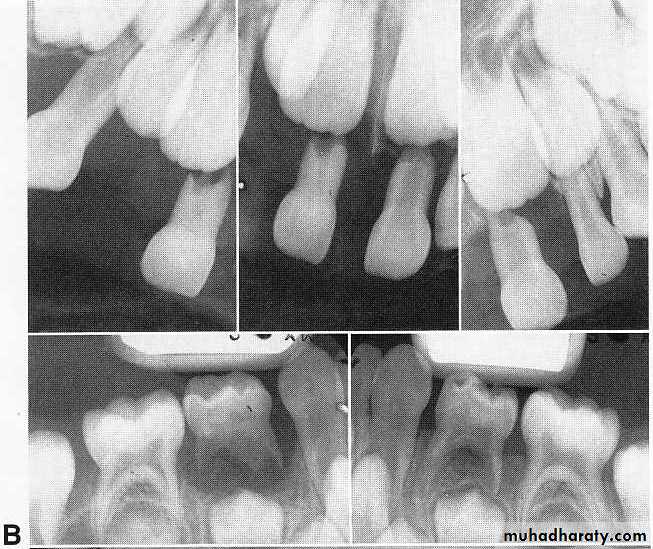

A, Prepubertal periodontitis in a 41/2-year-old girl. Loosening, migration, and spontaneous loss of the primary teeth occurred.

B, A generalized loss of alveolar bone can be

seen in the radiographs.